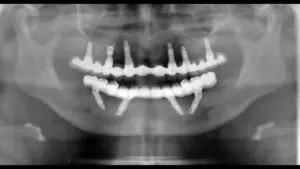

全口植牙是一項複雜且精密的手術,植牙醫師的技術經驗、嫻熟的植牙手法尤為重要,台北牙醫推薦–來德牙醫周承澤醫師,擁有紐約大學牙醫學院獲牙周病專科醫師資格,將美國先進植牙技術引進台灣,二十多年來累積豐富臨床、教學與研究經驗、無數成功案例,能結合研究理論與實務經驗,頂尖全口植牙技術值得您信賴。